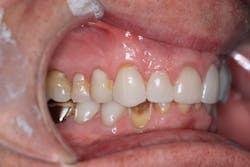

Radiographically, the first thing I noticed were the tabletopped occlusal surfaces (figures 1 and 2). Clinically, the same was evident, along with generalized wear facets on the posterior teeth (figures 3 and 4). The bite was deep (figures 5 and 6), and the lower anterior teeth had been worn down to half their original size. There were new ceramic crowns on nos. 21, 28, and 29. I also noted that there was an occlusal stop/resin on no. 13, but there was no significant effect on his occlusion as it was even on the right and left sides.